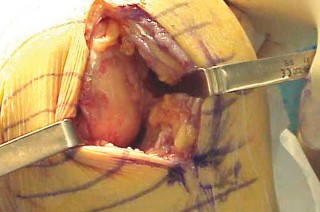

الشق الجراحي:

يُستخدم شق طولي في الجانب الإنسي (الداخلي) من الركبة. يجب أن يكون الشق كبيرًا بما يكفي لتوفير رؤية جيدة للمفصل الرضفي الفخذي وإمكانية التحويل إلى TKA.

- فتح المفصل (Arthrotomy): يكون الفتح خطيًا وموازياً لألياف الوتر الرضفي، ويمتد إلى عظم الظنبوب وإلى الجزء السفلي من الرضفة.

- تحرير الأنسجة الرخوة: يتم قطع الغضروف الهلالي لتحرير الأنسجة الرخوة من عظم الظنبوب، ويتم تطوير سديلة تحت السمحاق في نمط دائري حول الظنبوب. يُمدد هذا التحرير خلفيًا لضمان توازن الأربطة.